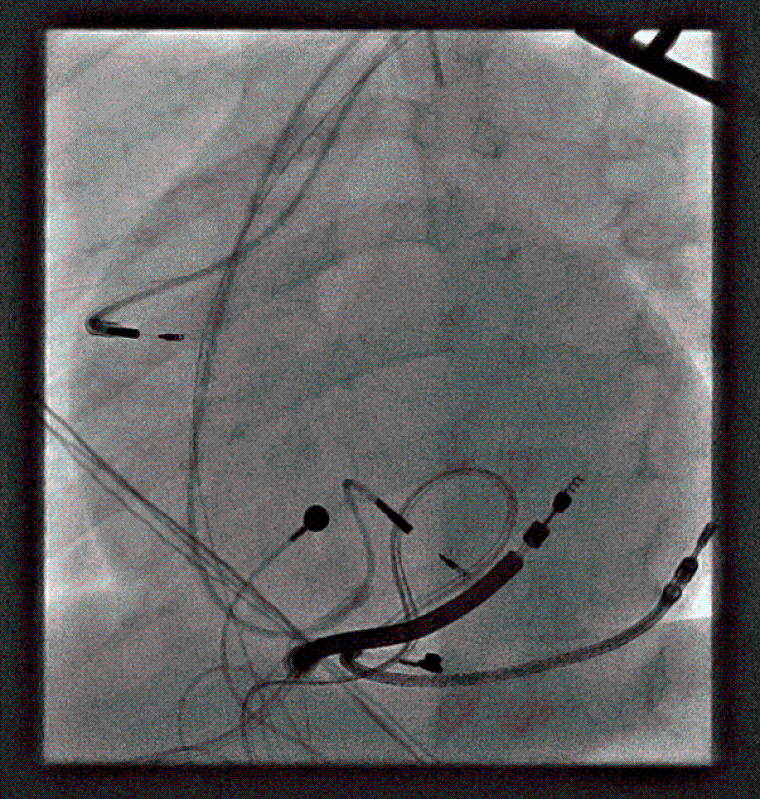

During the procedure, VF was induced with burst pacing after administering Isoprenaline. Despite adjusting the sensing threshold to 0.6mV, the ICD could not effectively detect VF, and a successful shock required changing the configuration from coil to can. Recognizing the device's inability to safely provide effective therapy during VF, a multi-disciplinary team meeting approved a "hybrid approach". The patient underwent ICD system revision, with the generator changed and left in an abdominal position. A transvenous atrial and ventricular pace-sense lead was inserted and tunnelled subcutaneously to the abdominal pocket, and an ICD shock coil was positioned subcutaneously anteriorly at the left parasternal site, with the shock set between the prior epicardial coil and the new subcutaneous coil (Image 3, 4a,b).

CC Vol 10 Picture3_Clinical case.png

CC Vol 10 Picture4A_Clinical case.png

CC Vol 10 Picture4B_Clinical case.png